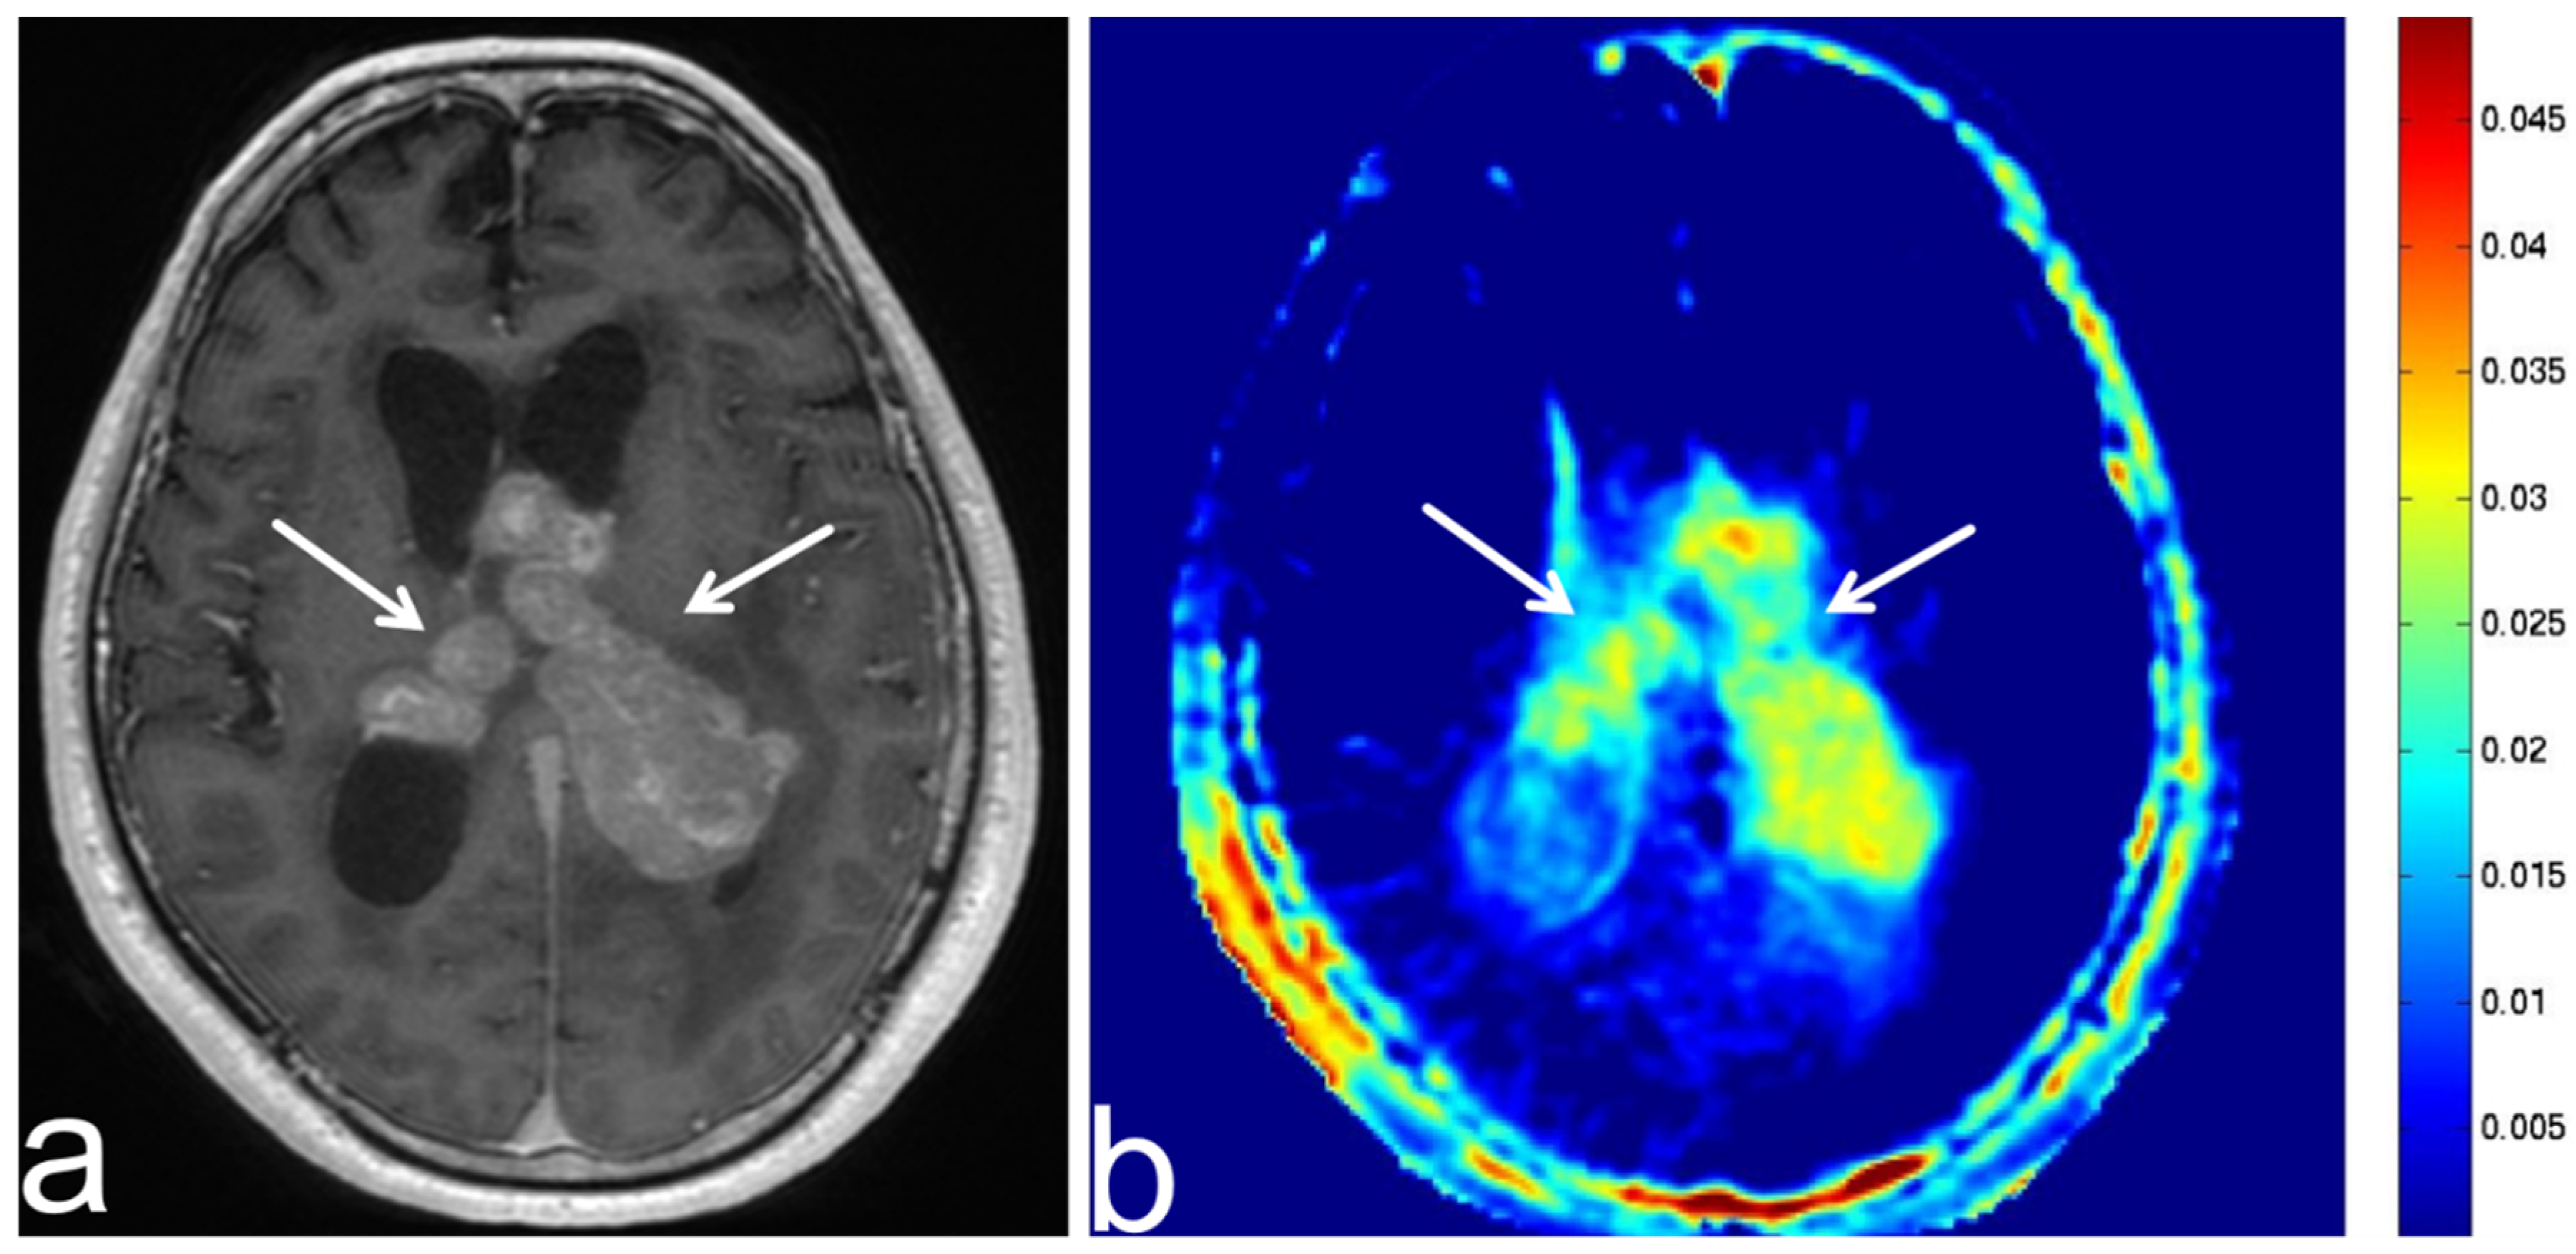

8.3. Tuberous Sclerosis Complex